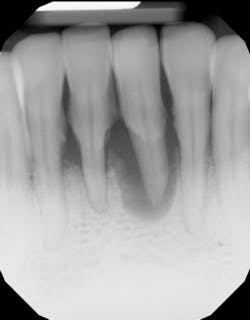

- Ensure tooth does not have a root fracture and check/refer for endodontic treatment if tooth is nonvital (figure 1)

- Splint tooth and adjust occlusion11 (figure 2)